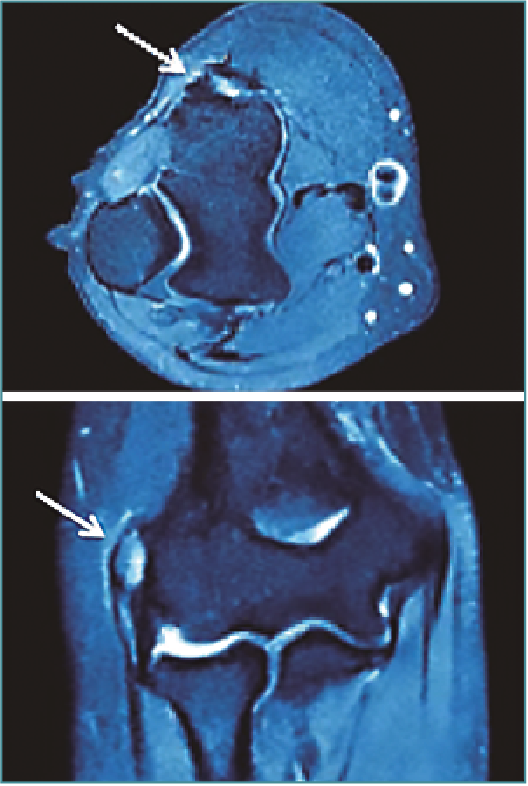

La resonancia magnética (RM) ayuda a confirmar el diagnóstico con una sensibilidad del 90-100% y una especificidad del 83-100%, siendo también útil para descartar patología articular o ligamentosa(10)(Figura 2).

Figura 2. Imagen de resonancia magnética de un codo derecho en el que se objetiva una señal hiperintensa en la región de las inserciones de los músculos extensores.